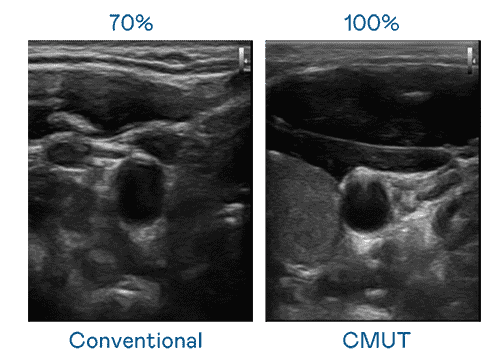

CMUT 技术是一种用电容式微机电元件来产生超音波讯号的技术。。与传统 PZT 压电式技术相比,,,,CMUT 频宽增加 30%,,更宽频的超音波讯号让影像解析度大幅提升,,,是实现高影像品质医疗超音波扫描、、、促进精准医疗发展的关键技术。。。。

大频宽带来超清晰影像

超音波影像的解析度高低,,首先取决于探头能发出的讯号频宽。。红龙扑克 CMUT 可提供高清晰的超音波讯号,,提供高频宽、、高灵敏度、、、、影像纹理细节更高的超音波影像,,协助医护人员缩短影像判读时间及利用精准的医疗影像进行诊断。。